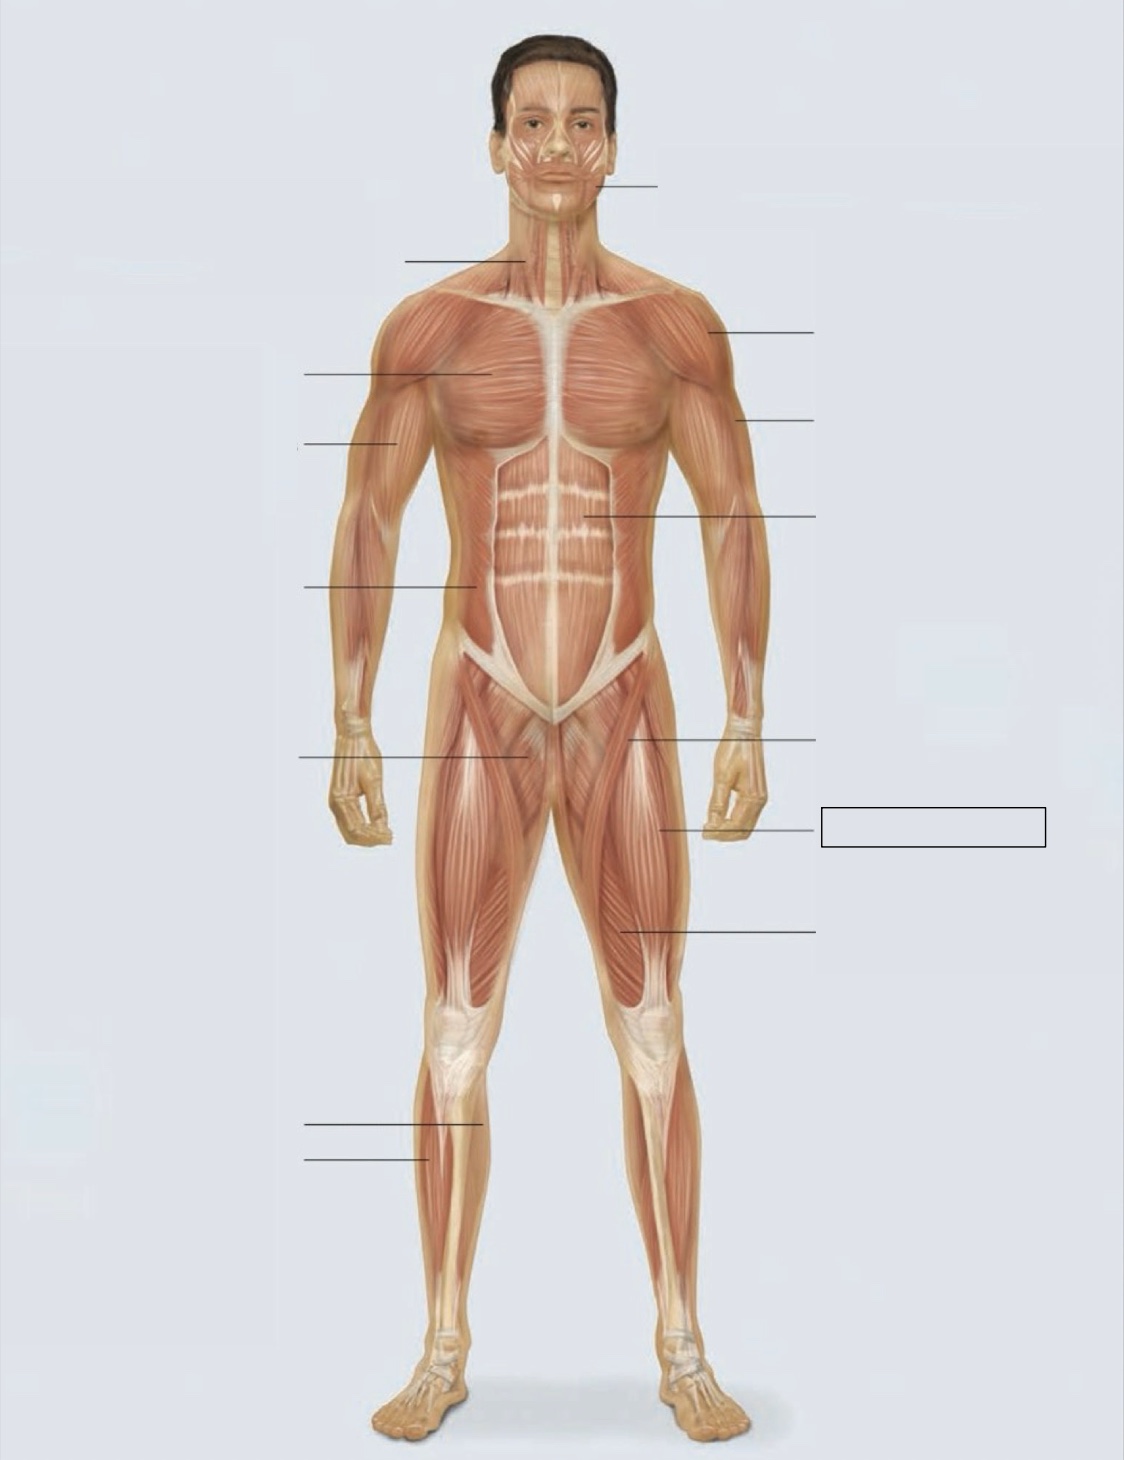

masseter

deltoid

triceps

rectus abdominis

sartorius

quadriceps femoris